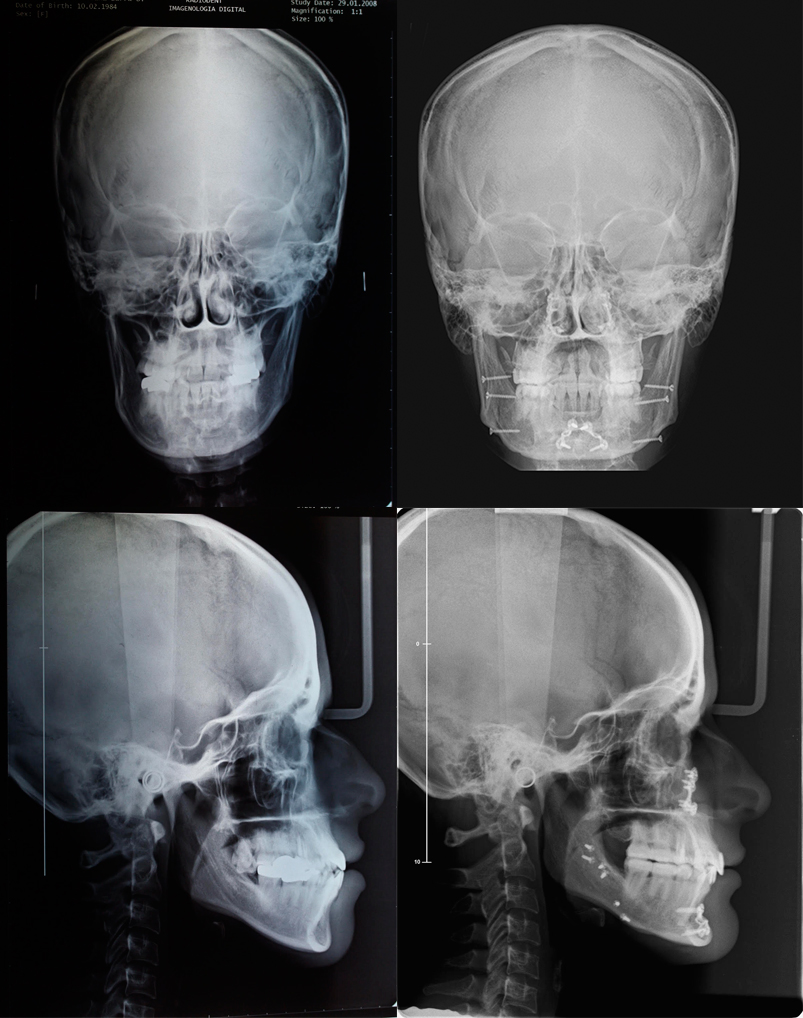

Paciente con progenie, asimetria esqueletal y piezas dentarias con falta de la capa de esmalte.Tratamiento: Ortodoncia, Cirugía y Rehabilitación. (V. Barra)